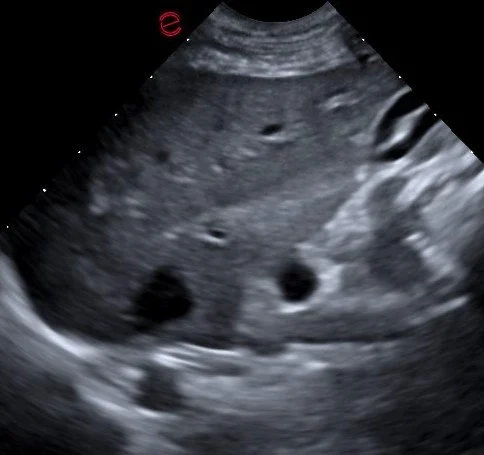

Abdominal Ultrasound with Specialist Consult

A complete abdominal ultrasound includes all organs and surrounding tissues of the abdominal cavity, including:

• Liver, gallbladder, billiary system

• Spleen

• Kidneys and urinary bladder

• Available reproductive organs- uterus, ovaries; testes, prostate

• Adrenal glands

• Gastrointestinal tract, including the pancreas

• Surrounding tissues including lymph nodes, mesentery, and vasculature

All abdominal ultrasounds include a specialist report from an internal medicine specialist or radiologist.

Fine needle aspirates (FNA) of masses can be obtained upon request, however sedation and recent bloodwork will be required. Abdominocentesis and cystocentesis can also be requested.